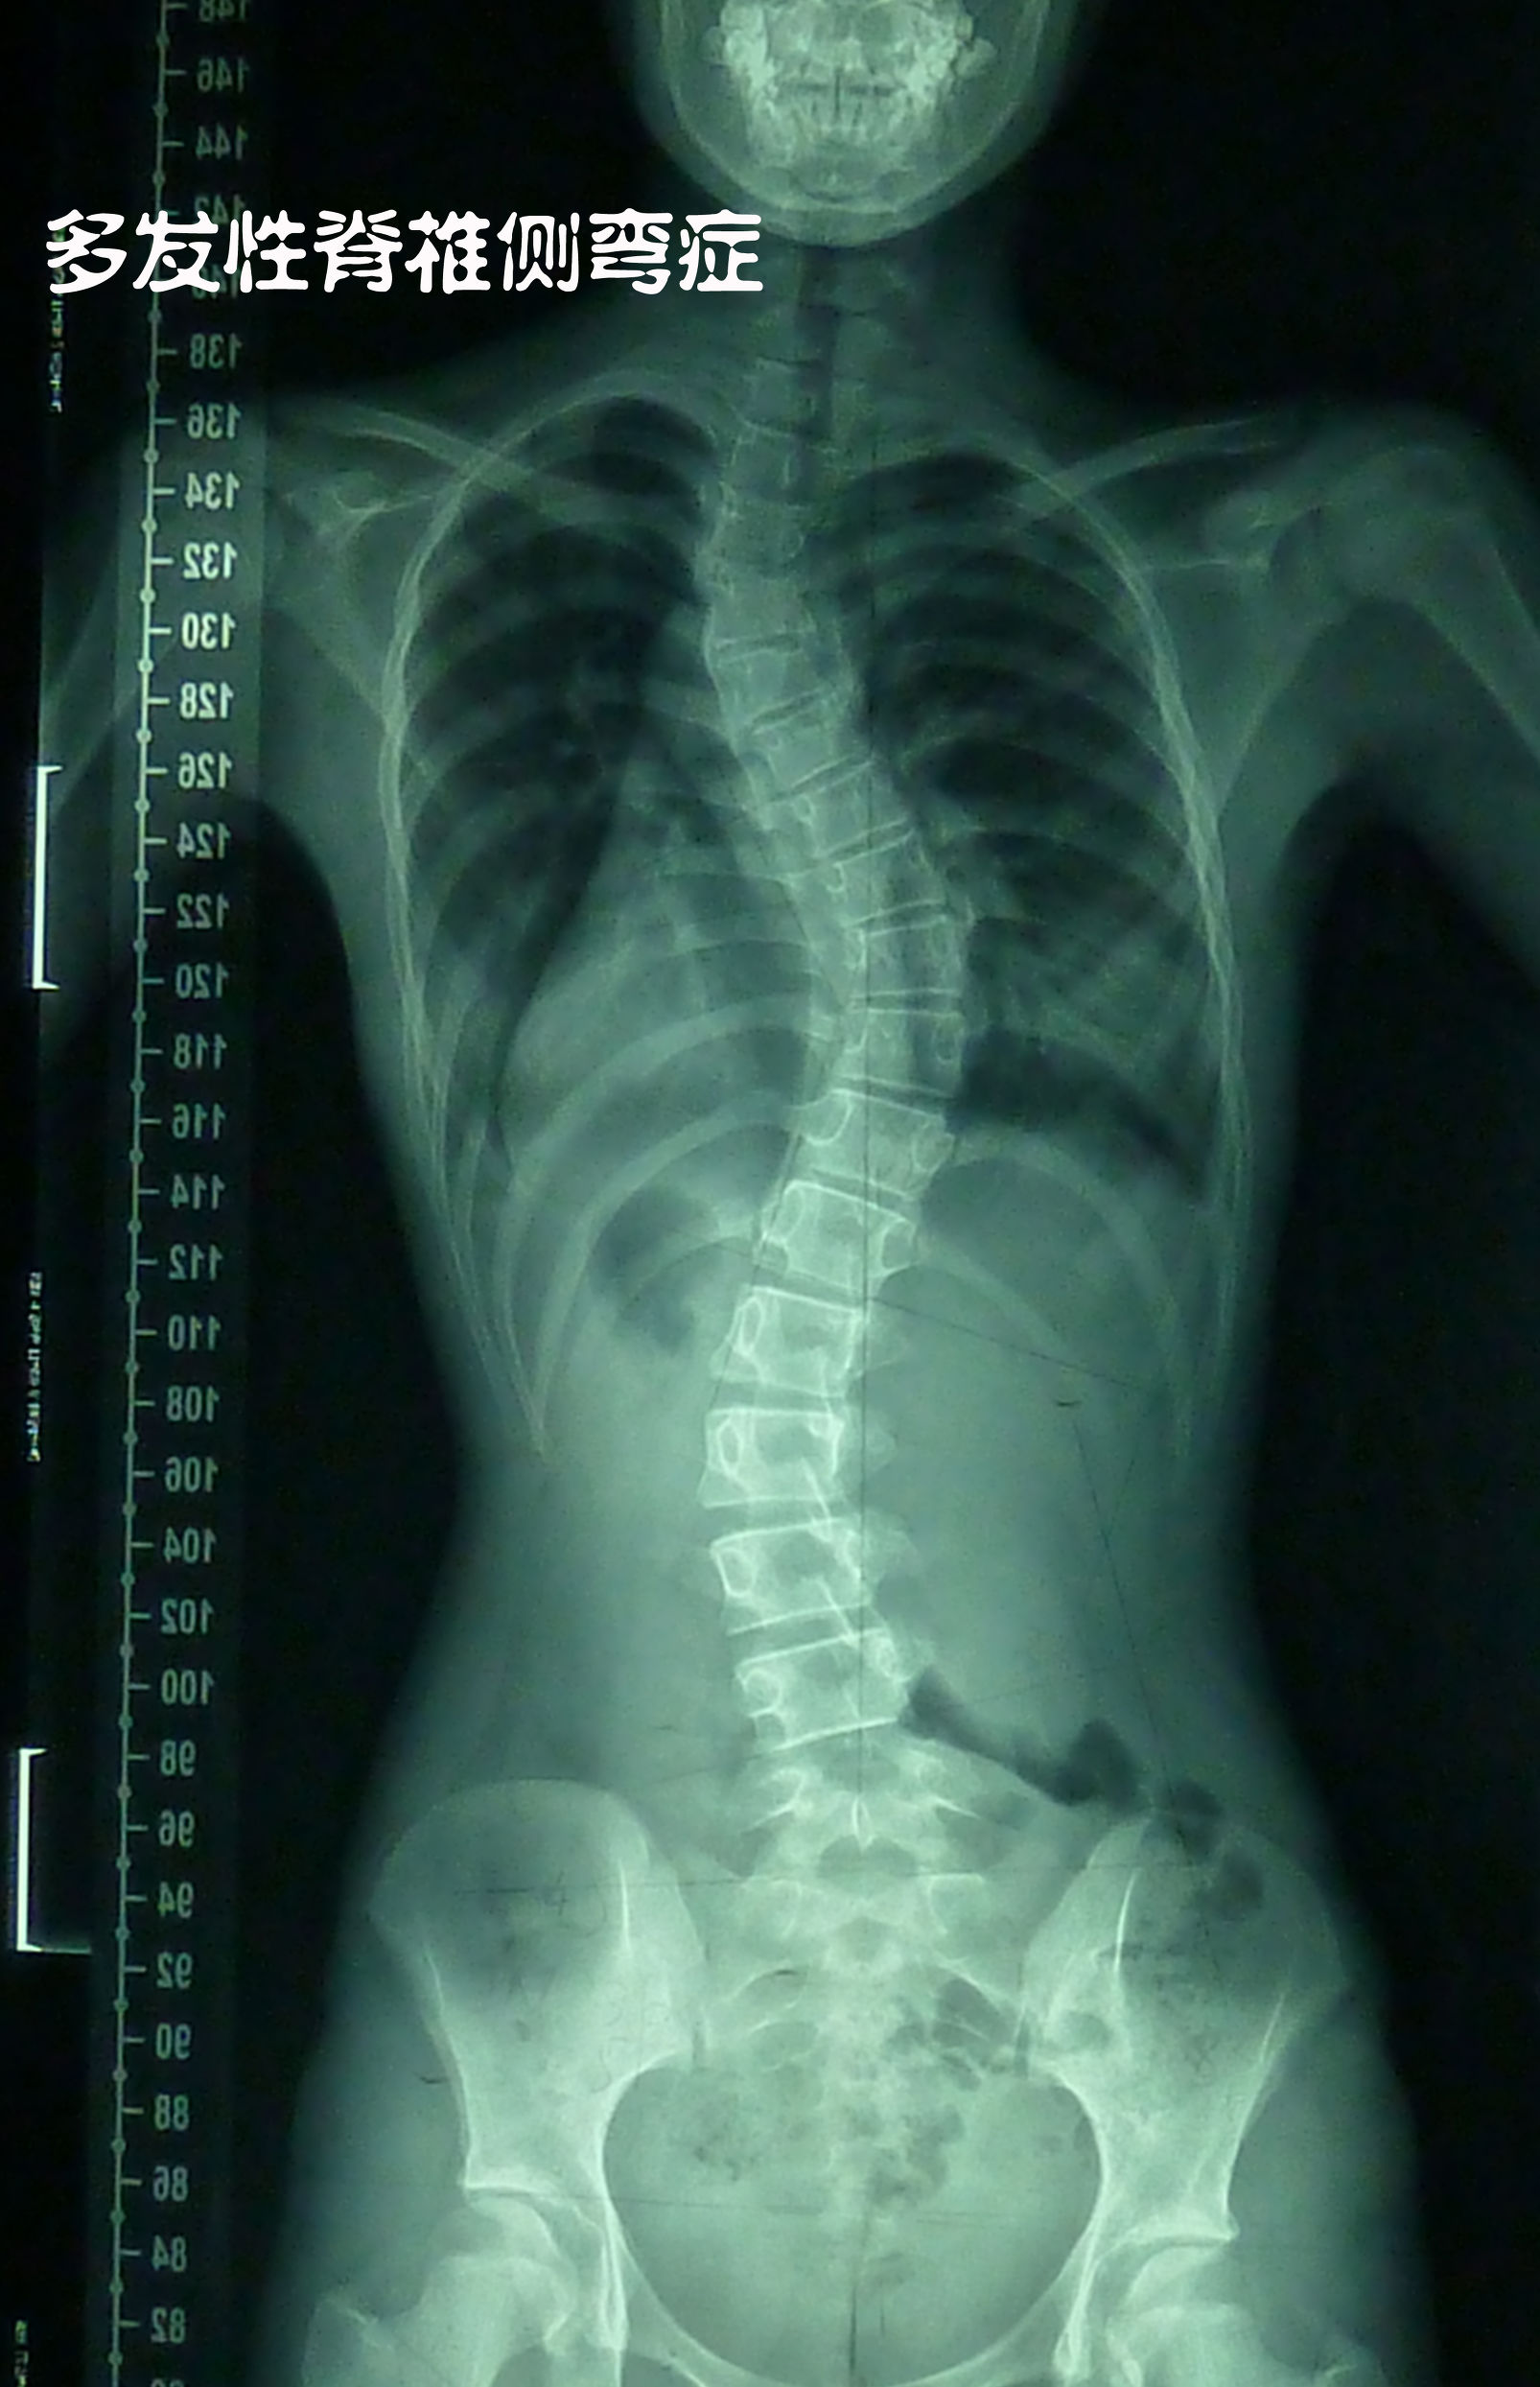

然而,现实中很多人的脊柱都歪了,呈现出“S”型的弯曲,这就是我们讲的脊柱侧弯。

从以下图片来看,脊柱是弯曲的,而从脊柱外的轮廓(身体外形)来看,基本上是比较正常的,很难看得出身体是歪的。因为“S”型的弯曲比较对称,所以整个体型看起来就是很对称的。这个人脊柱侧弯比较厉害,还有的人弯曲没有这么大,那在外形上就更看不出来了。也正因如此,很多人活了半辈子了都不知道自己有脊柱侧弯,有得人是因为颈椎不好,或腰椎不好,去做检查才得知自己有脊柱侧弯。